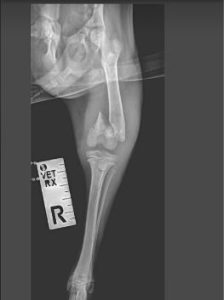

Jamie and his two siblings were found abandoned in a derelict school house. Desperation was etched on their sweet faces and their bodies were full of fleas and their skin covered in demodex. Jamie was found to be less active than his siblings and after x-rays was found to have a fractured femur. He has now had an operation and is recovering from his ordeal alongside his brothers